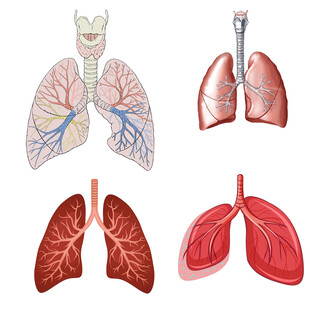

人体肺部解剖结构示意图 共享分:100

人体肺部解剖结构示意图 共享分:100 -

肺部结构与解剖示意图 共享分:100

肺部结构与解剖示意图 共享分:100 -

人体肺部解剖结构示意图 共享分:100

人体肺部解剖结构示意图 共享分:100 -